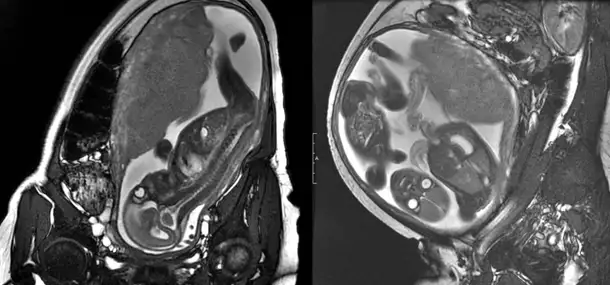

Utilizing the exact same technology used for imaging all other body parts, we are able to perform an MRI to look at the fetus, or unborn child, in the uterus during second- and third-trimester pregnancies. This allows us, the radiologists, to add valuable information to the findings already identified on obstetrical ultrasound. Fetal MRI is of particular value when looking at the brain of the fetus and has allowed us to identify and better characterize abnormalities even before the child’s first breath. Plans and treatments can begin weeks to months before the birthdate, allowing the best care to start as soon as possible.